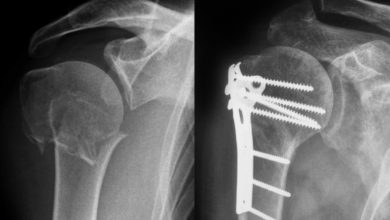

Ortopedi

Omurga kırıkları belirti vermeden ortaya çıkar !